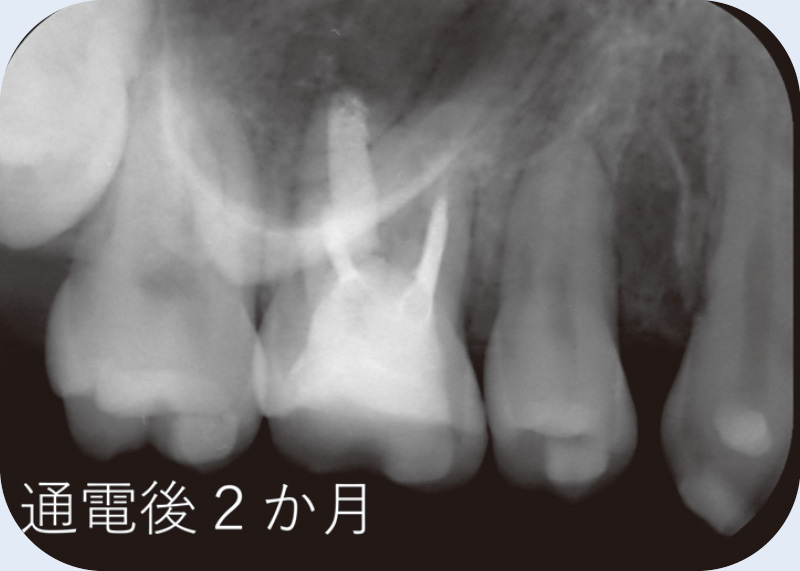

![[写真] 初診時](/academic/dentalmagazine/wp-content/uploads/sites/2/2025/11/195-3_photo10.jpg)

![[写真] 通電後2か月](/academic/dentalmagazine/wp-content/uploads/sites/2/2025/11/195-3_photo11.jpg)